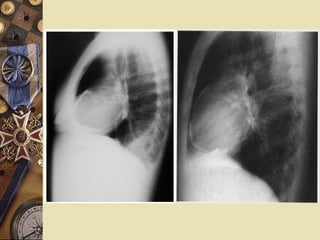

PERICARDITIS CONSTRICTIVA

NORMALNORMAL CONSTRICTIVACONSTRICTIVA

1-2mm1-2mm

1-2cm1-2cm

PERICARDITIS CONSTRICTIVA  50%diagnóstico patológico inespecífico  TBC  Neoplasia  Purulenta ETIOLOGIAETIOLOGIA Engrosamiento pericárdico : 1-2 cmEngrosamiento pericárdico : 1-2 cm Grosor normal : 1-2mmGrosor normal : 1-2mm